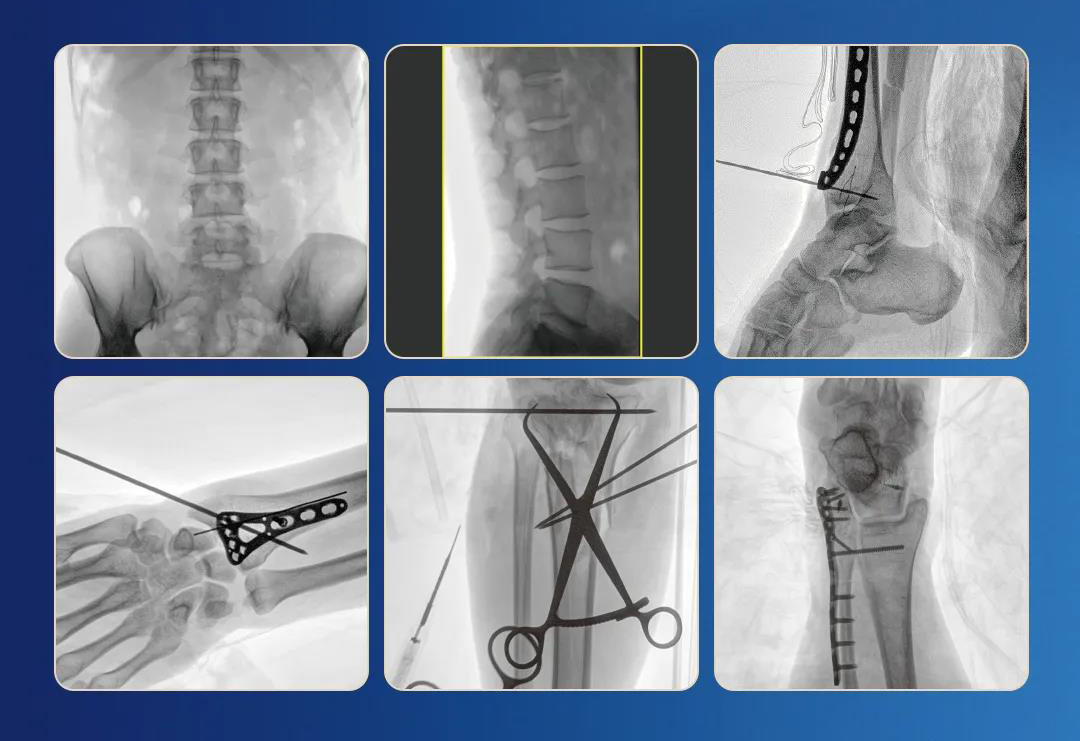

一、臨床應(yīng)用

1.關(guān)節(jié)手術(shù)

2.創(chuàng)傷手術(shù)

3.脊柱手術(shù)

4.疼痛治療